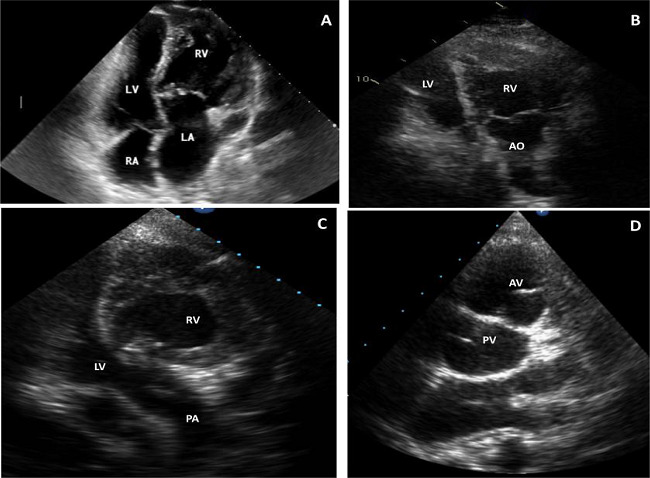

Echocardiography: The peculiar discordant atrioventricular and ventriculoarterial connections and the abnormal spatial relationship of the great arteries are usually seen, sometimes as the first diagnostic clue. The initial segment of the great vessels run in parallel, and the ventricular arrangement is more often side-by-side or superior-inferior rather than left/right, anterior/posterior as found normally. The VSD is usually perimembranous, and its precise features are important when surgical intervention is considered. It is also important to determine the location, extent, and type of valvar and/or subvalvar PS (fibrous diaphragm, membranous septum aneurysm, or accessory mitral tissue). In some patients, TR is noted to arise from inferiorly displaced tricuspid valve leaflets, anatomically similar to Ebstein’s anomaly. Routine follow-up of these patients is important as the TR in this setting tends to progress and can be associated to RV dysfunction.

RV function assessment is crucial. Late presentation with pre-existing RV dysfunction has been reported to impact survival. Echocardiographic assessment might be challenging, particularly due to the complex morphologic features of the RV cavity, including coarse trabeculations in the medial and apical regions. However, reliable echocardiographic parameters do exist including tricuspid annular plane systolic excursion (or TAPSE), fractional area changing, tricuspid ring tissue doppler S’ wave, myocardial performance Tei index, and global longitudinal strain by the speckle tracking method[18]. Recent studies have highlighted the benefits of assessing the longitudinal functional parameters, and the global longitudinal strain has been reported to be a highly sensitive marker of RV dysfunction in patients with RV ejection fraction < 45%[19-21](Figure 2).

![Bidimensional echocardiograms in patients with congenitally

corrected transposition of the great arteries. A) 16-year-old

patient, four-chamber view. Discordant atrioventricular connections

plus moderate tricuspid regurgitation (TR) and mild pulmonary

stenosis (PS); B) 35-year-old patient, apical view. Left-sided right

ventricle (RV) connected to aorta (AO) plus mild TR/PS after

Rastelli operation; C and D) 24-year-old patient with mild TR.

Apical view (right-sided left ventricle [LV] connected to pulmonary

artery [PA]) (C) and short axis parasternal view (aortic valve [AV]

anterior and to the left of pulmonary valve [PV]) (D). LA=left

atrium; RA=right atrium.](../0102-7638-rbccv-37-04-0534-gf02.jpg)